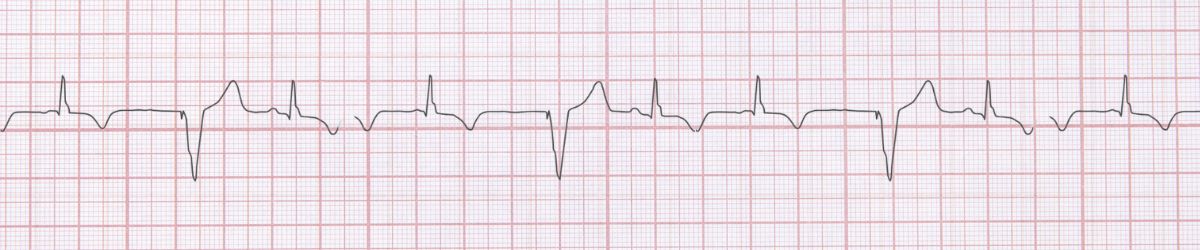

Image Premature Ventricular Contractions ECG Example Figure 1: Premature Ventricular Contractions - Characteristic ECG Pattern

• Wide QRS >0.12s

• Premature beat

• Compensatory pause

• No P wave for PVC